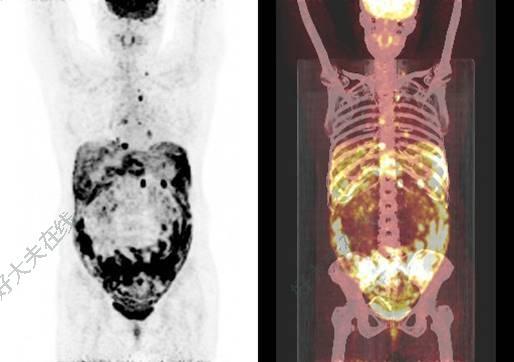

今天一位腸癌的老太太,由于年事已高,擔(dān)心化療的毒副作用,咨詢是否有化療以外的治療方案,這樣不能耐受化療或不愿意化療的病人其實還不少。為了滿足這一部分患者的需求,我們從2年前就開始相關(guān)探索和研究,在腸癌中開展了APICAL研究,在一線晚期腸癌患者中采用無化療的靶向+免疫方案,經(jīng)過一系列的病例觀察,發(fā)現(xiàn)取得了不錯的效果,包括針對既往認(rèn)為對免疫療效不好的肝轉(zhuǎn)移病灶,也取得了不錯的效果(見下圖)?,F(xiàn)在APICAL研究正在進(jìn)行,而且靶向和免疫藥物都是免費的哦,如果有合適的病人可以和我們聯(lián)系。